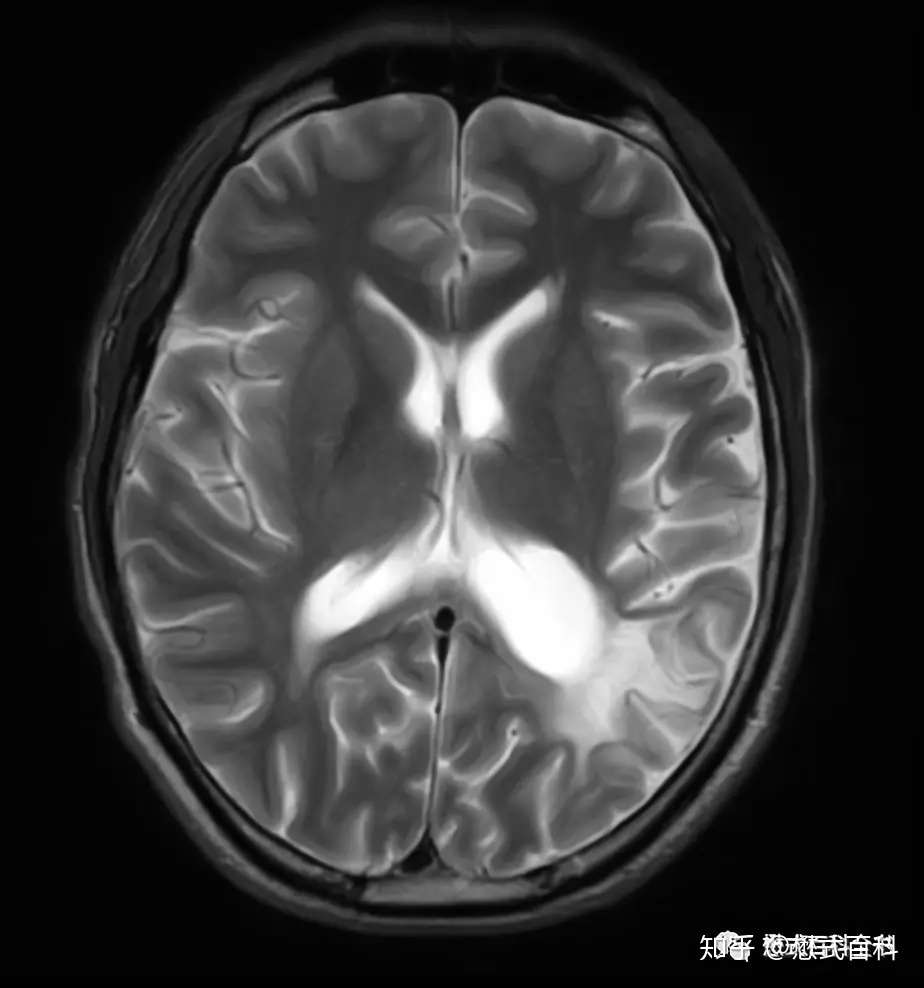

ガドリニウム:MRIで造影といえばこれ。 超磁性体酸化鉄粒子 SPIO:肝網内系をターゲットとした造影剤である。SPIOはKupffer細胞に貪食されリソソームにクラスター化される家庭でT2*緩和時間およびT2緩和. くはない3).mriでは,鉄沈着による局所の磁場 の不均一により,t1,t2及びt2*緩和時間が 短縮する特性を利用して肝内鉄沈着の評価が可 能である.特にt2及びt2*とそれらの逆数であ るr2及びr2*は鉄濃度と比例して変化するた 一口メモ 図3 肝生検組織所見. 頭部mriの見方です。 基本は 水 = 脳脊髄液 を見ます。 脳脊髄液は脳室や脳の表面にあります。 t1なら黒 t2なら白です。 話が難しいのは mriに….

〈medix vol.50〉 41 1.はじめに mri検査において基本シーケンスはt2強調画像とt1強調 画像である。かかりつけ医の医療の場において、診断能向上の. 頭部MRI の基礎 -頭部MRI で撮られる各画像について- 友愛会南部病院 仁井田 明 要旨 現在、日常的に撮影されている頭部MRI(Magnetic resonance imaging :磁気 共鳴画像法)画像にはT1 強調像(T1WI)、T2 強調像(T2WI)、プロトン密度強 調像(PDWI)あるいはFLAIR(FLuid-Attenuated Inversion Recovery)像. 3T MRIの組織コントラスト能の特徴 T1強調画像 de Bazelaireらの研究 1) によると,腹部領域における3Tと1.5Tの緩和時間の違いは,肝臓,脾臓,膵臓では,3TでT1値が著明に延長するのに対し,筋肉では緩和時間に差がなく,結果的に,3Tでは肝臓,膵臓,筋肉でのT1値の差が少なくなる。.

脑横断面解剖图